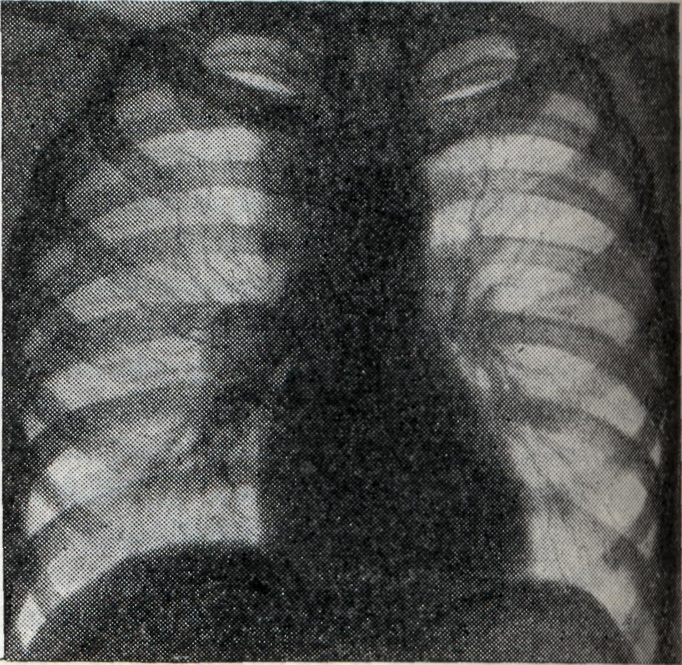

Рис. 1.

Двусторонний опухолевидный бронхаденит. Тени корней увеличены, контурируются довольно чёткими волнообразными линиями (рентгенограмма).

При опухолевидной форме Б. перифокальные явления в прилегающей лёгочной ткани обычно отсутствуют. Тень корня увеличена, менее структурна, отдельные сосудистые стволы корня плохо различимы (рис. 1).

Проекции бронхов менее отчётливы, тень корня почти сливается с тенью средостения. Наружная волнообразная или бугристая граница деформированного корня проецируется в виде отчётливой, хотя и не всегда резкой линии, что зависит от отсутствия или наличия воспалительных изменений в капсуле лимф, узлов. При одностороннем опухолевидном Б. изменения корня противоположного лёгкого менее выражены (рис. 2), на стороне поражения лёгочный рисунок несколько усилен, прилежащие листки междолевой плевры уплотнены (рис. 3).